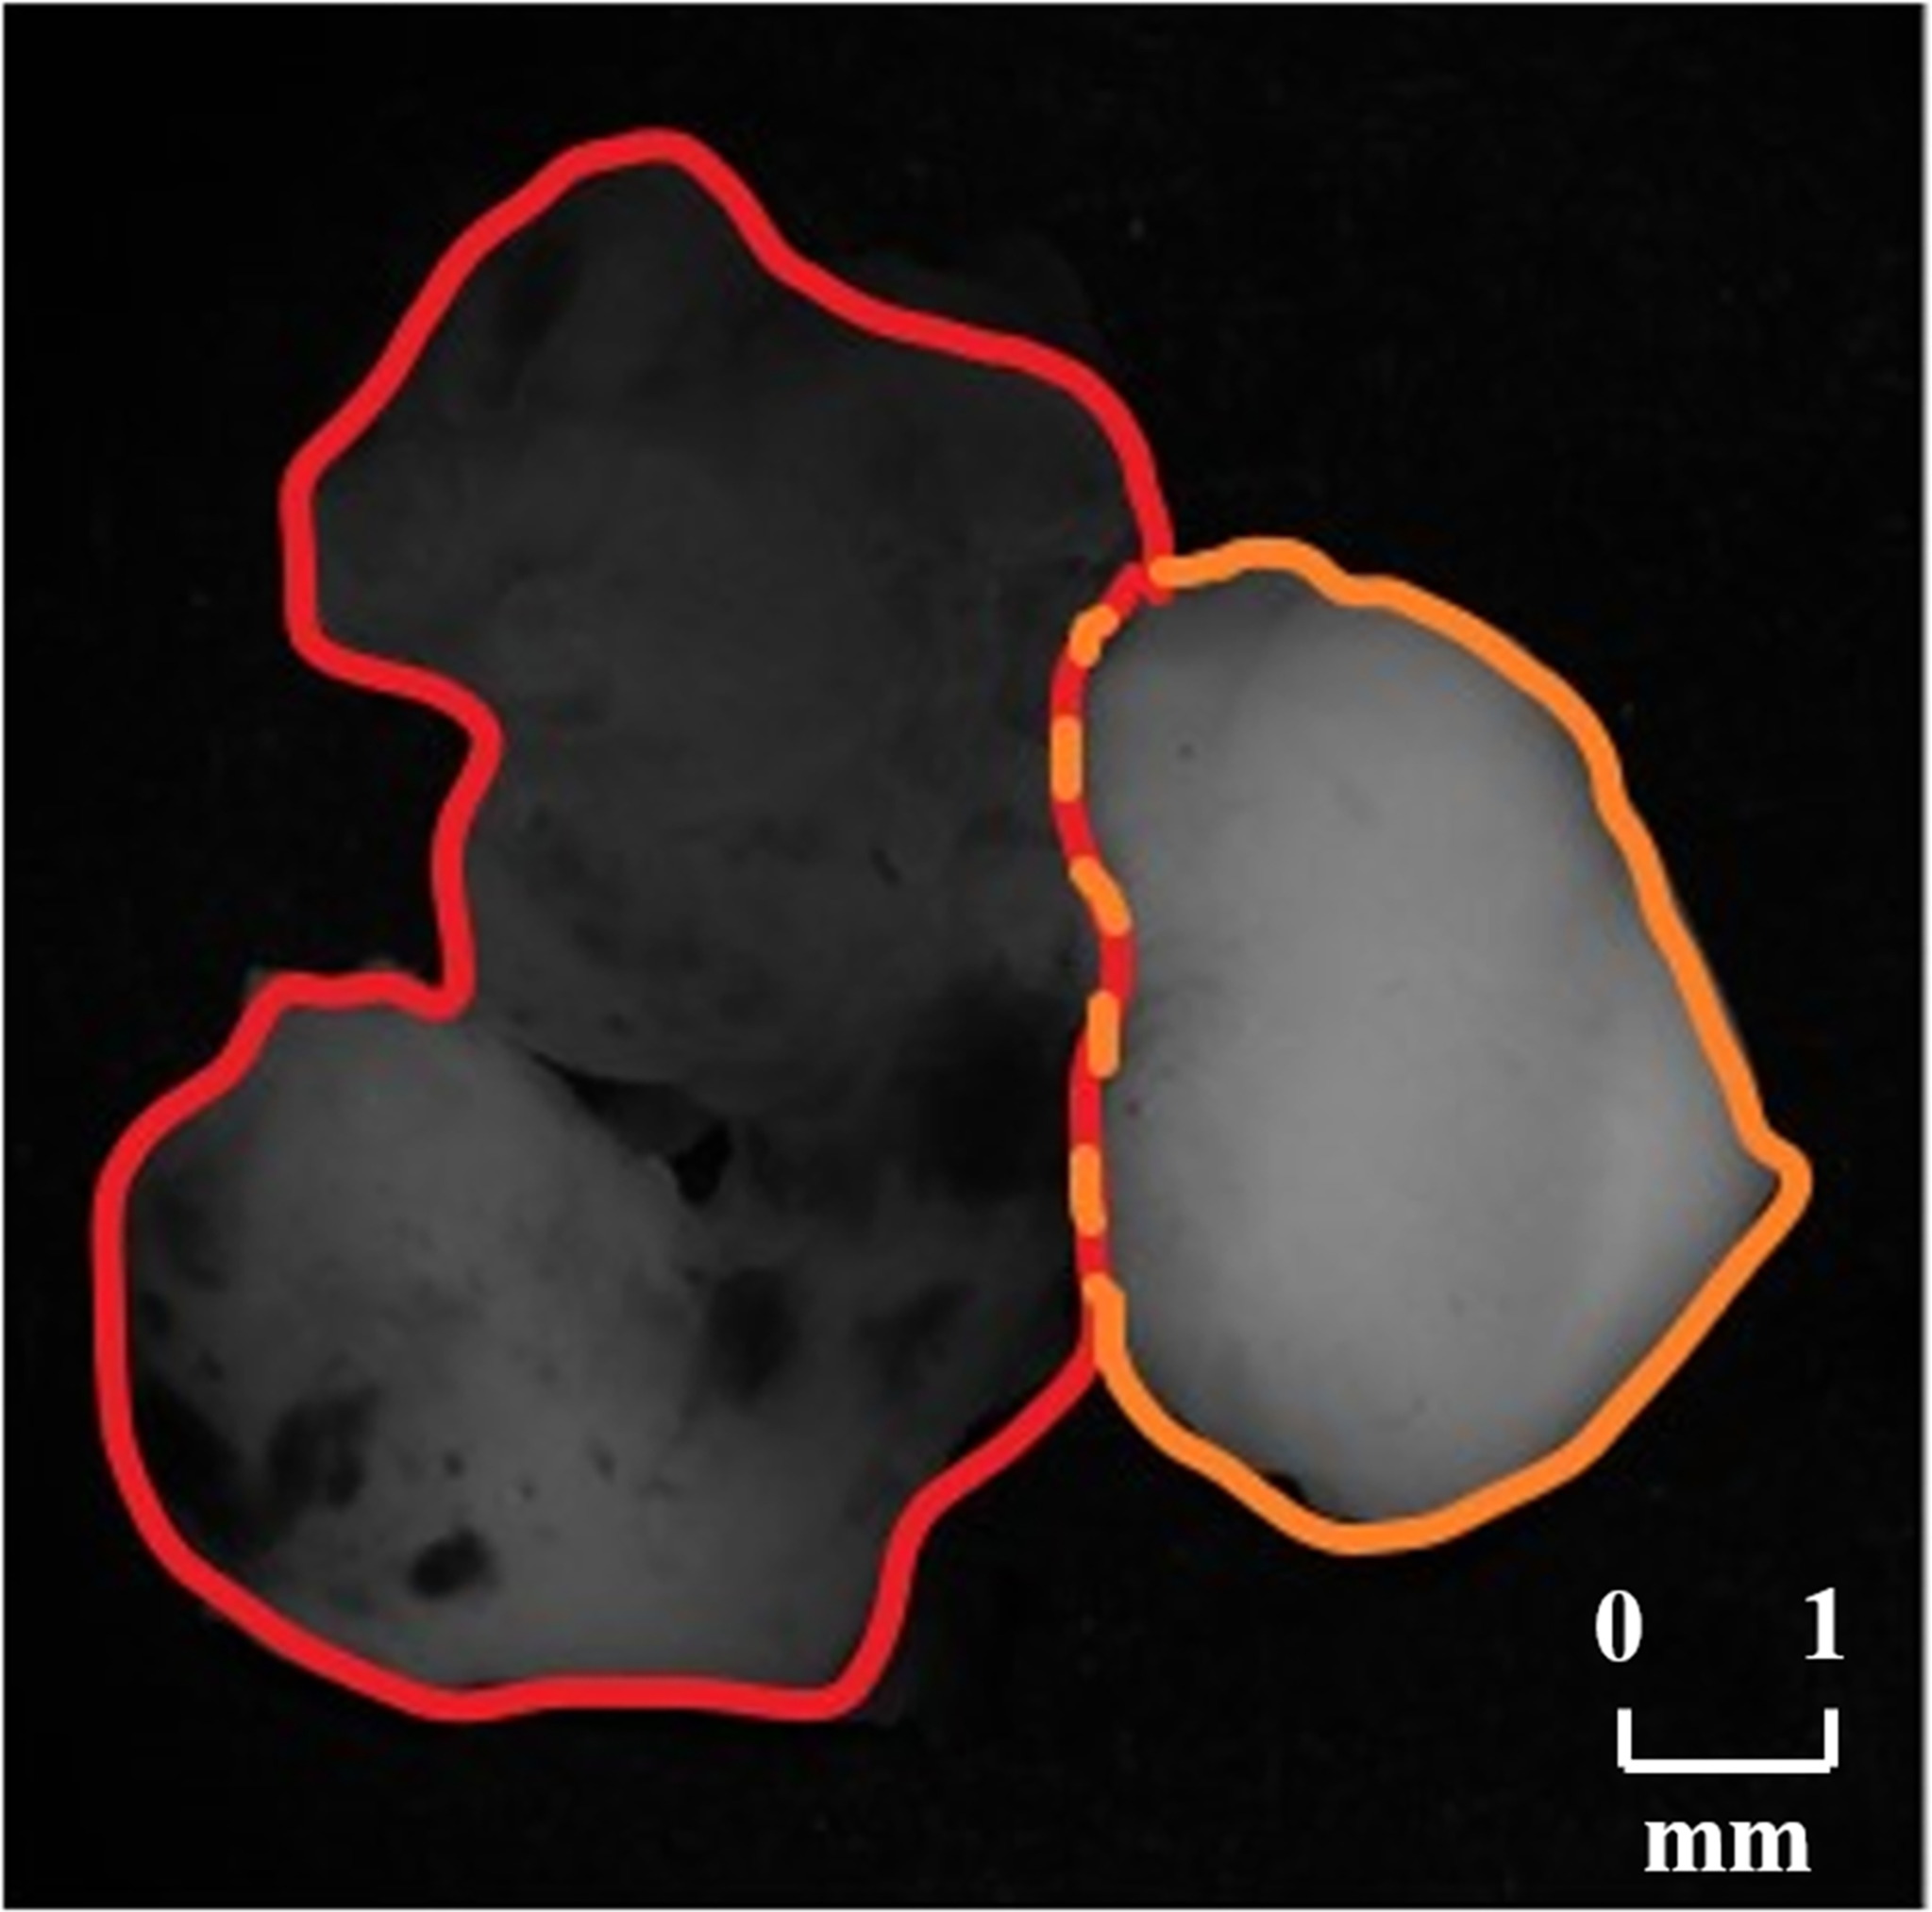

In order to testify the potential application of PIT on human brain glioma samples, especially when it was used to identify brain glioma from non-glioma brain tissue during surgical operation, the methods mentioned above were used on the human brain glioma samples: 20 formalin-soaked unstained GBM samples with brain white matter region (theoretically contains no glioma cells) used in this study were provided by Department of Neurosurgery of General Hospital of Tianjin Medical University, and the samples shown in Figure 2 were grayscale image of the formalin-soaked unstained thick bulk of the GBM samples with non-GBM brain tissue cut from the patient’s cranial cavity during the surgery, with two regions marked and boundary delineated. The GBM sample is cut purely from the center of the tumor. It ensures that the polarization characterization of the GBM is reasonable, which is the first step and foundation of the further research about the identification of GBM residual during operation. However, with the imaging conditions strictly controlled, various intraoperative interference factors (such as blood) can be eliminated in in vitro glioma PIT experiments. For pathological comparisons, the corresponding hematoxylin-eosin (HE)-stained 6-μm-thick slices of GBM and non-GBM were also prepared and are shown in Figure 3 to evaluate the PIT images and reveal the relationship between the pathological features and PIT images of the samples, showing that the GBM region was with a darker stained color (which means high cellular density, and denser and larger cell nuclei) than the non-GBM region. The use of the clinical glioma samples in this study was approved by the Administrative Committee on Animal Research of the Shenzhen International Graduate School, Tsinghua University. All experiments and methods were performed in accordance with the relevant guidelines and regulations.

Figure 2

Grayscale images of the GBM sample with non-GBM brain tissue, where the GBM region is marked with red boundary delineated and the non-GBM region is marked with orange boundary delineated.